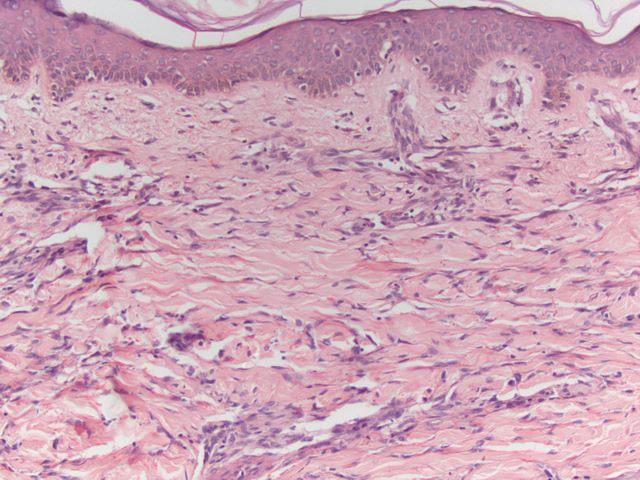

417 -- image13.jpg